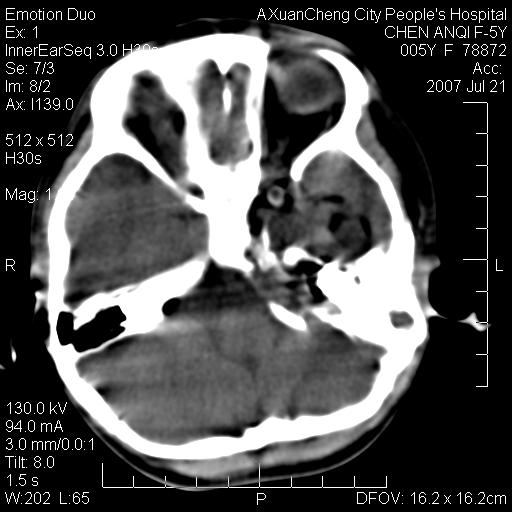

标题: PED0273:5岁,左耳流脓痛疼一周,颅底骨质破坏 [打印本页]

标题: PED0273:5岁,左耳流脓痛疼一周,颅底骨质破坏

患儿5岁,左耳流脓痛疼一周,左外耳道肉芽组织填塞 软组织窗显示病灶内结节状低密度影为气体密度

左侧中耳炎并胆脂瘤,左颞骨岩部骨质破坏并颅内感染积气。

考虑化脓性中耳乳突炎伴胆脂肪瘤形成并左颞叶感染,不除外合并嗜酸性肉芽肿.